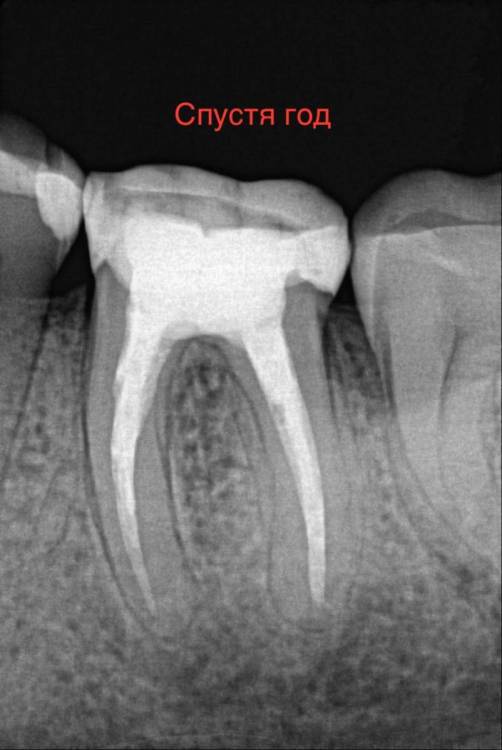

chacraborti Опубликовано 13 февраля, 2024 Поделиться Опубликовано 13 февраля, 2024 Делали ре-ендо зуба 36, прошел год прикрепляю снимок до и после. Прошло ли воспаление у верхушки корня? Ссылка на комментарий

kramer Опубликовано 13 февраля, 2024 Поделиться Опубликовано 13 февраля, 2024 Прошло 1 Ссылка на комментарий